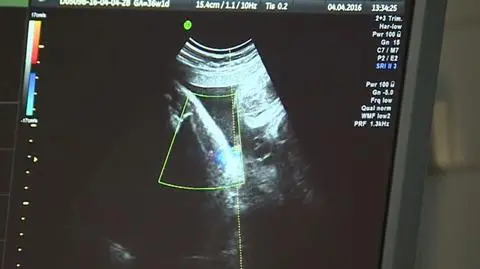

Za przepisami, które zakwestionował Trybunał Konstytucyjny są nie tyko paragrafy i interpretacje. Są przede wszystkim konkretne ludzkie historie, dramaty i cierpienie dziecka, matki i całych rodzin. Do tej pory szanse przygotowania się na ryzyko dawały badanie prenatalne. Anna Wilczyńska.